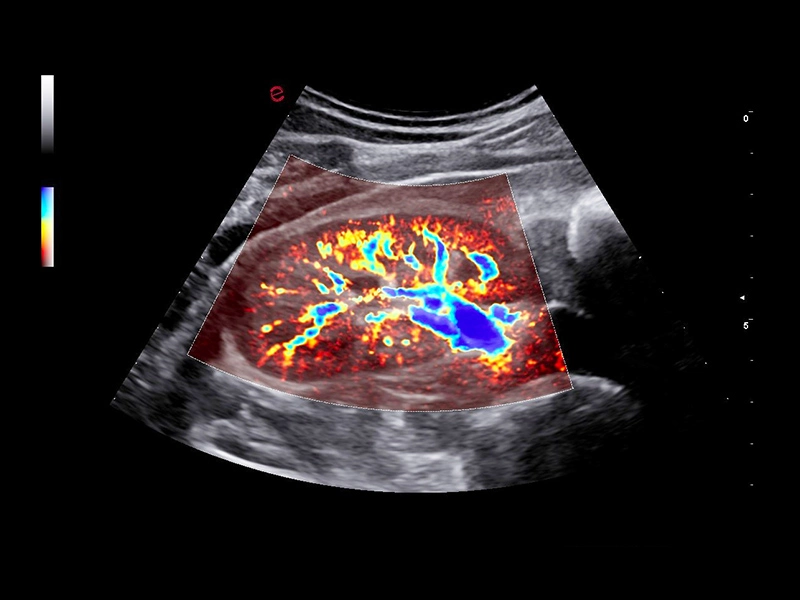

MyLab™C30 - MICROV-NEW

MyLab™C30 - MICROV-NEW